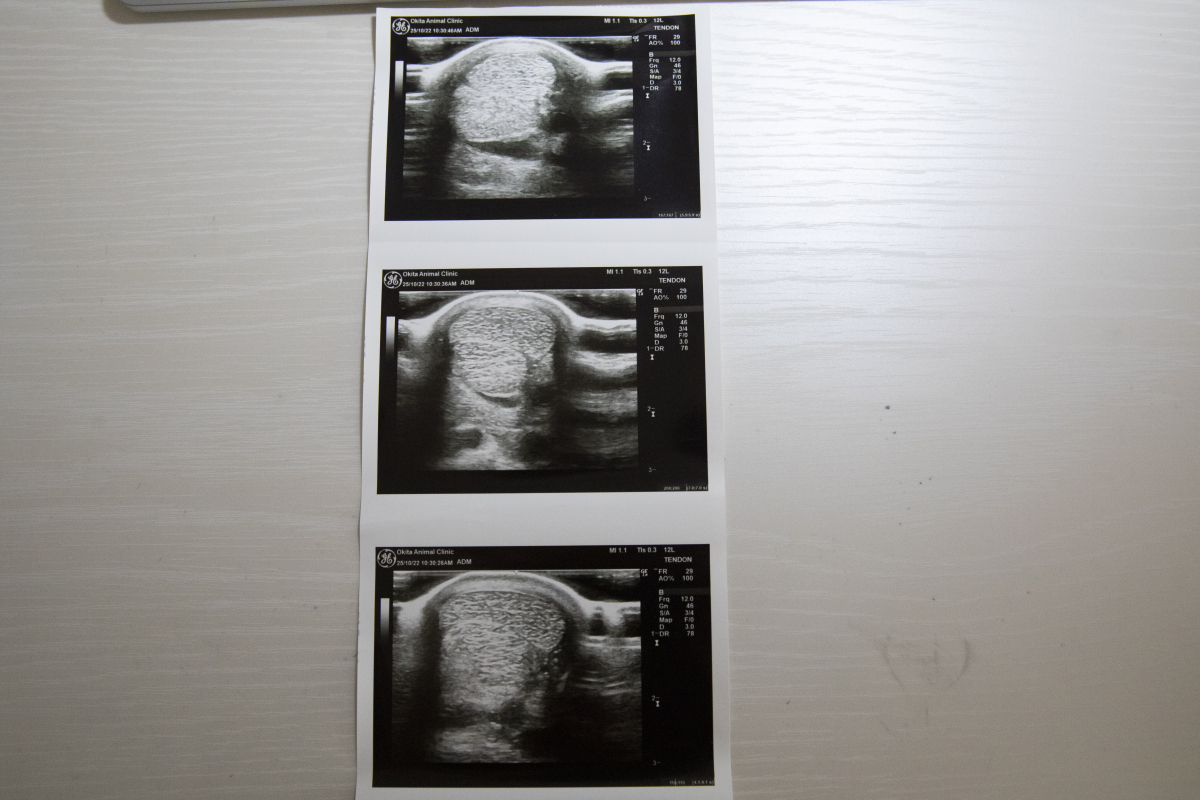

1200mではややスピード不足の印象でしたが、距離を延ばした前走は前半から行きっぷりが良すぎたほどで、かなり噛んでしまって失速したのもやむを得ません。結果的にブリンカーが効きすぎたようで、外してリズム良く折り合えれば結果は違っていたでしょう。現状は脚元にも配慮しながらの調整ですので、固まって攻め込めるようになれば変わってくるはずです。エコー検査のため、10/22に両前脚の毛を刈っています。(ホッカイドウ競馬・桧森邦夫調教師)

※右前屈腱部に慢性的な腫れが見られ、中央退厩時と前走後にエコー検査を受けましたが、腱周囲の腫れが見られたものの、腱自体の炎症は見られないとの診断でした。